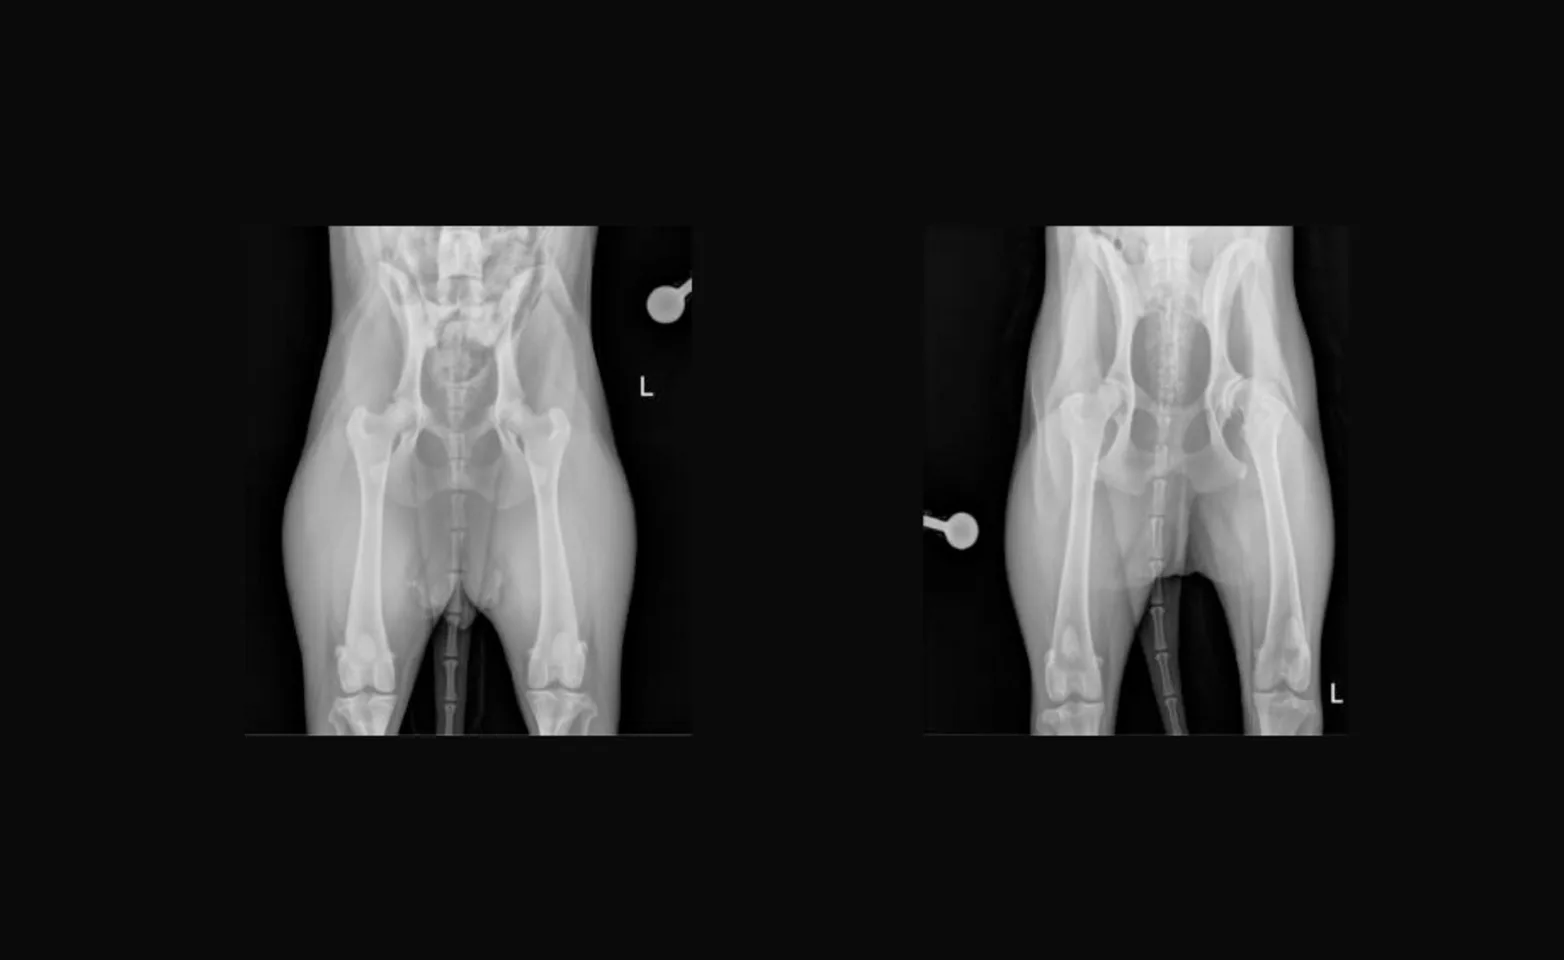

The most common reason a THR is recommended is to treat pain and disability associated with hip dysplasia and associated arthritis (Figures 1 [Normal Canine Hips] & 2 [Bilateral Hip Dysplasia and Subsequent Arthritis; left worse than right]). Other reasons for total hip arthroplasty include traumatic hip luxations that cannot be maintained in place following manual reduction and also some fractures of the femoral head and neck. Ideal candidates are at least 10 months or older and weigh greater than 40 lbs (breed dependent).

Hip dysplasia is a developmental disorder that occurs in dogs who are predisposed to the condition which is often characterized by laxity of the ball and socket joint. This creates malformation and abnormal pressures on the cartilaginous surfaces of the joint which leads to erosion, boney deposits, and ultimately pain of the joint and hind limb lameness. This pain can manifest as the classic “bunny hopping” gait, reluctance to jump or climb stairs, and overall decreased activity levels. Both hips are usually affected although one is often worse or more painful than the other. However, only approximately 20% of dogs with bilateral hip disease will require bilateral total hip arthroplasty in their lifetime.